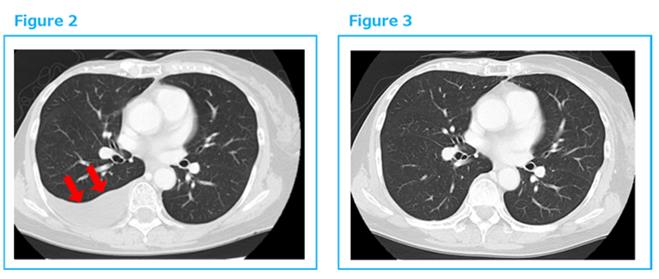

2014年底出現胸水,穿刺診斷復發。于是2015年1月再開始αβT細胞治療,每2周1次共6次,之后每個月1次。到2016年3月胸水完全消失。